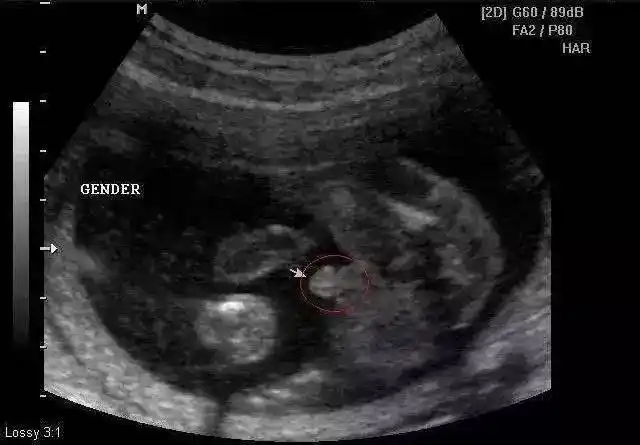

37岁女歌手徐佳莹官宣二胎,透露孩子性别,写新歌赠给未来女儿